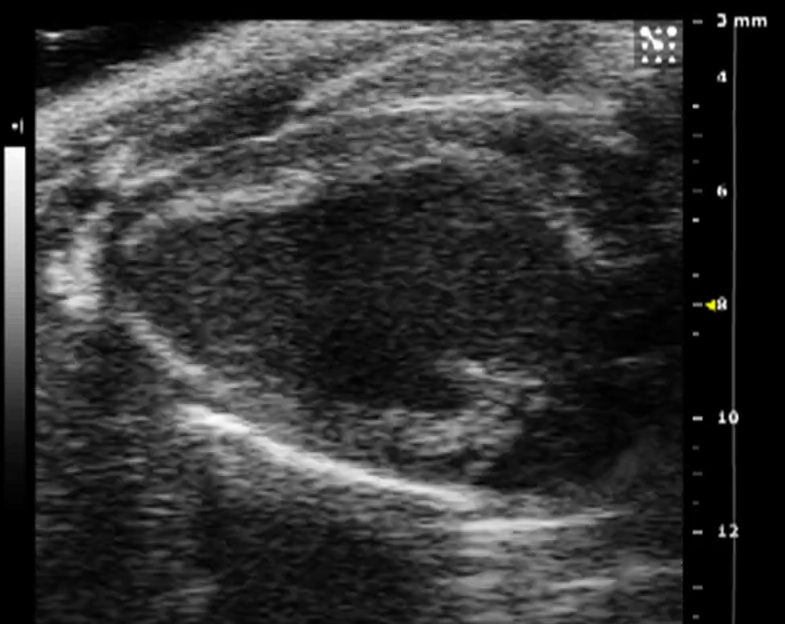

PCIC houses the ultrasound Vevo 2100 (Fujifilm Visualsonics Inc.). This unique technology allows acquiring real time images with high resolution for structural and functional imaging. It is perfect for assessing heart anatomy and function (echocardiography) in mice and rats. Transducers ranging from 13 to 55 MHz are available for imaging of vascular tumors (up to 14mm) to large tumors (<250g) along cardiovascular imaging. Multiple modes allow for additional analysis of blood flow and pressure.

Examples of ultrasound images (blood flow analysis) acquired by our Vevo 2100